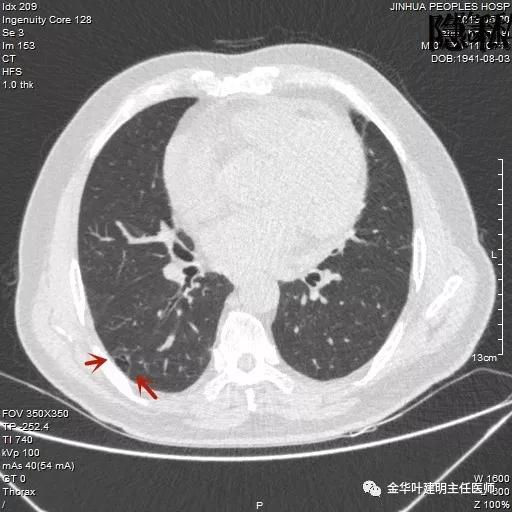

以上是2016年5月的片子,此处有非常小而淡的空腔性病灶,边缘略显磨玻璃,但仍说不上肯定的恶性。